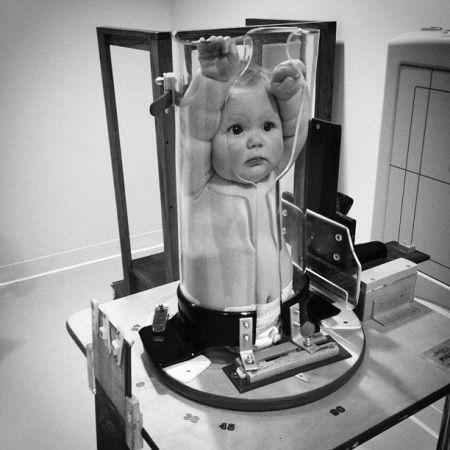

Щоб виявити у недоношеної дитини пневмонію, використовують:

- Рентген-обстеження. На рентгенограмі в місцях запалення виявляють затемнення.

- Лабораторні дані. У крові дитини з пневмонією буде відзначено паличкоядерних зсув, зниження гемоглобіну, зменшення числа тромбоцитів, лейкопенію. Крім клінічного аналізу крові діткам з підозрою на пневмонію призначають вірусологічне або бактеріологічне обстеження, аналіз сечі і дослідження газового складу крові.